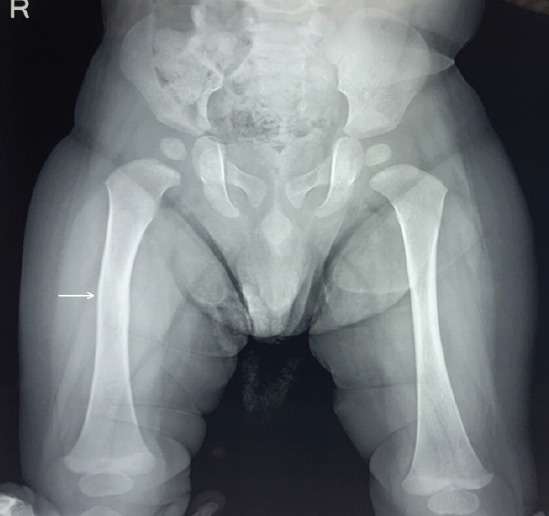

Case report: A 3915 g male child born at 38 weeks and 4 days of gestation to a primigravida aged 31 years by emergency Lower Segment Cesarean Section for Premature Rupture of Membrane with breech presentation. During extraction, the newborn sustained a fracture to his right femur shaft. X-rays confirmed the diagnosis. The fracture was treated successfully with a toe-groin cast for 25 days with complete healing.